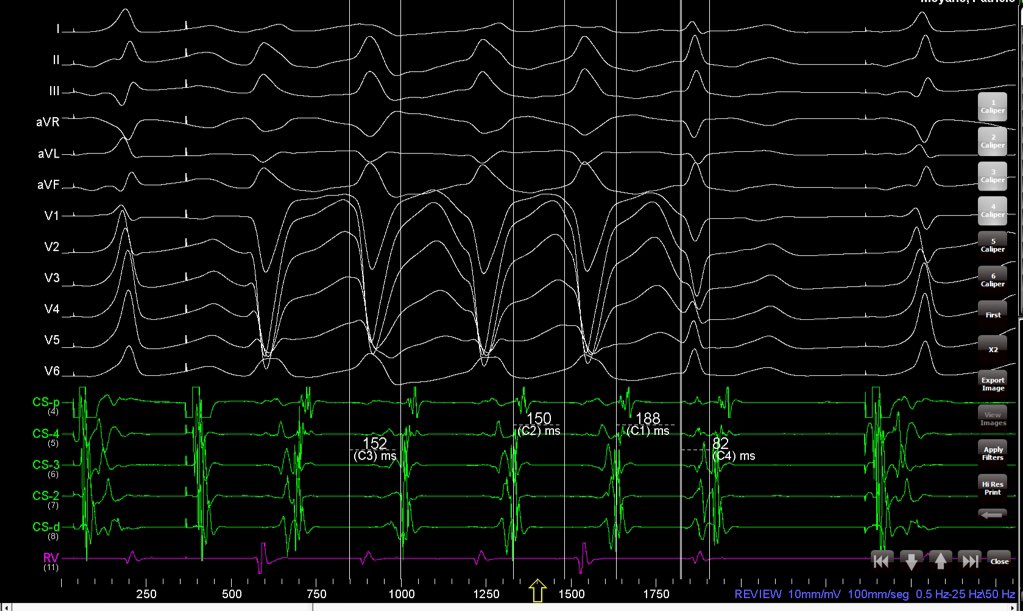

It is really easy to understand. WCT has a longer VA than NCT. When LBBB resolves, VA is shorter and AH longer, producing AV block after first beat after QRS normalization. In this case, there is no His. Measurements are made from CS no QRS onset.

It is really easy to understand.

WCT has a longer VA than NCT. When LBBB resolves, VA is shorter and AH longer, producing AV block after first beat after QRS normalization.

In this case, there is no His.

Measurements are made from CS no QRS onset.